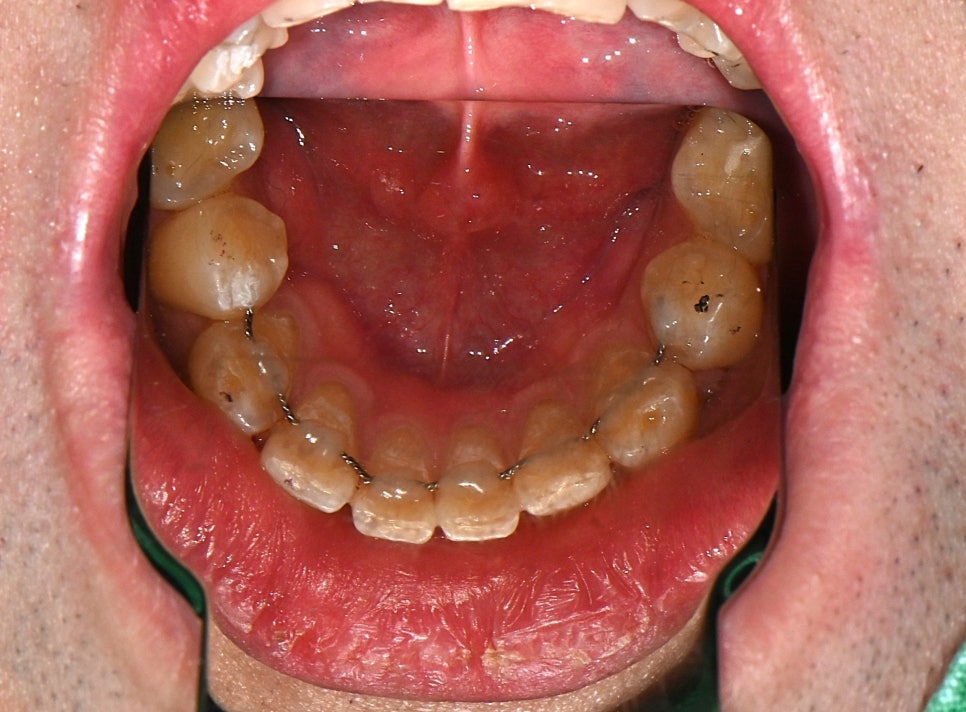

This is the result after the remade fixed retainer was attached.

We removed the old remaining wire and attached a newly made, precisely crafted retainer after taking a new impression.

It fits closely to the teeth and helps prevent the alignment from becoming irregular again in the future.